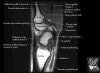

손목 관절의 MRI 단면 영상

- Coronal section

Coronal T1 imaging evaluates bone marrow signal (ex. increased in avascular necrosis) and the relationship of the osseous structures to each other (ex. scapholunate disassociation).